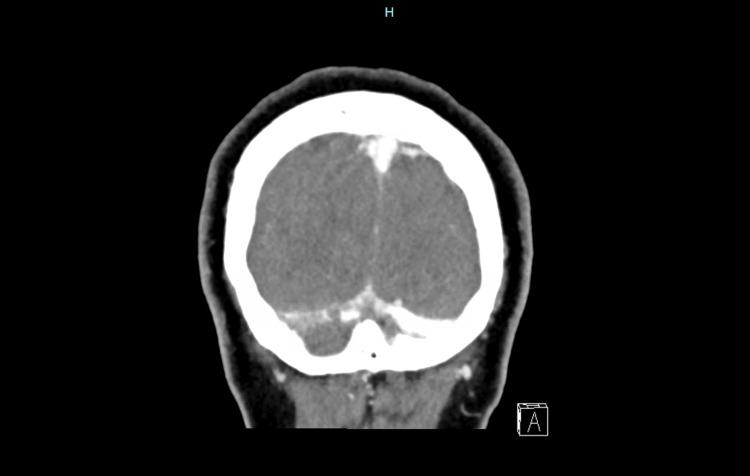

严重脱水引发的脑静脉窦血栓形成

Cerebral Venous Sinus Thrombosis Triggered by Severe Dehydration.

Cerebral venous sinus thrombosis (CVST) is the causative factor in a small proportion of strokes. It primarily affects individuals aged less than 55 years, with up to two-thirds of cases affecting females. It can be precipitated by a myriad of transient or permanent risk factors that result in a prothrombotic state. Diagnosis of CVST requires a high index of clinical suspicion as the presenting symptoms are often vague and include headaches, visual deficits, seizures, etc. Computed tomography or magnetic resonance venography are sensitive imaging diagnostic modalities. The majority of patients have a favorable prognosis. It is important to pursue thrombophilia work-up after the resolution of an acute episode as some cases are secondary to an underlying malignancy.

摘要

脑静脉窦血栓形成(CVST)是一小部分中风的致病因素。它主要影响年龄小于55岁的个体,高达三分之二的病例为女性。它可由导致血栓形成前状态的众多短暂或永久性危险因素引发。CVST的诊断需要高度的临床怀疑指数,因为其表现症状往往模糊,包括头痛、视力缺陷、癫痫发作等。计算机断层扫描或磁共振静脉造影是敏感的影像学诊断方法。大多数患者预后良好。在急性发作缓解后进行血栓形成倾向检查很重要,因为有些病例继发于潜在的恶性肿瘤。